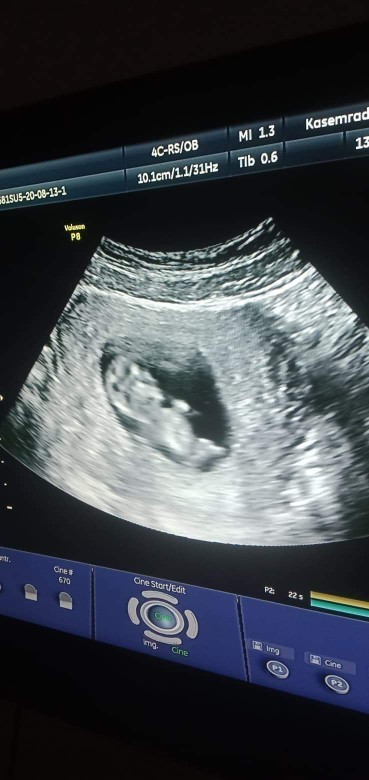

11 สัปดาห์

11 สัปดาห์ ซาวด์มาเจอลูกแบบนี้ถือว่าเขาตัวใหญ่ไหมคะหรือปกติ

11week3day จ้า